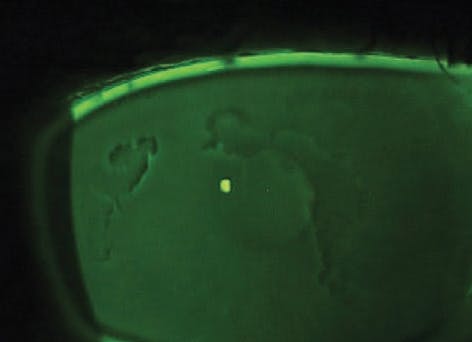

THE DYSTROPHY WITH THREE NAMES